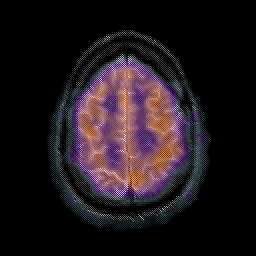

Glioma overlay -- Slice #23

[Home][Help][Clinical] Slice 23